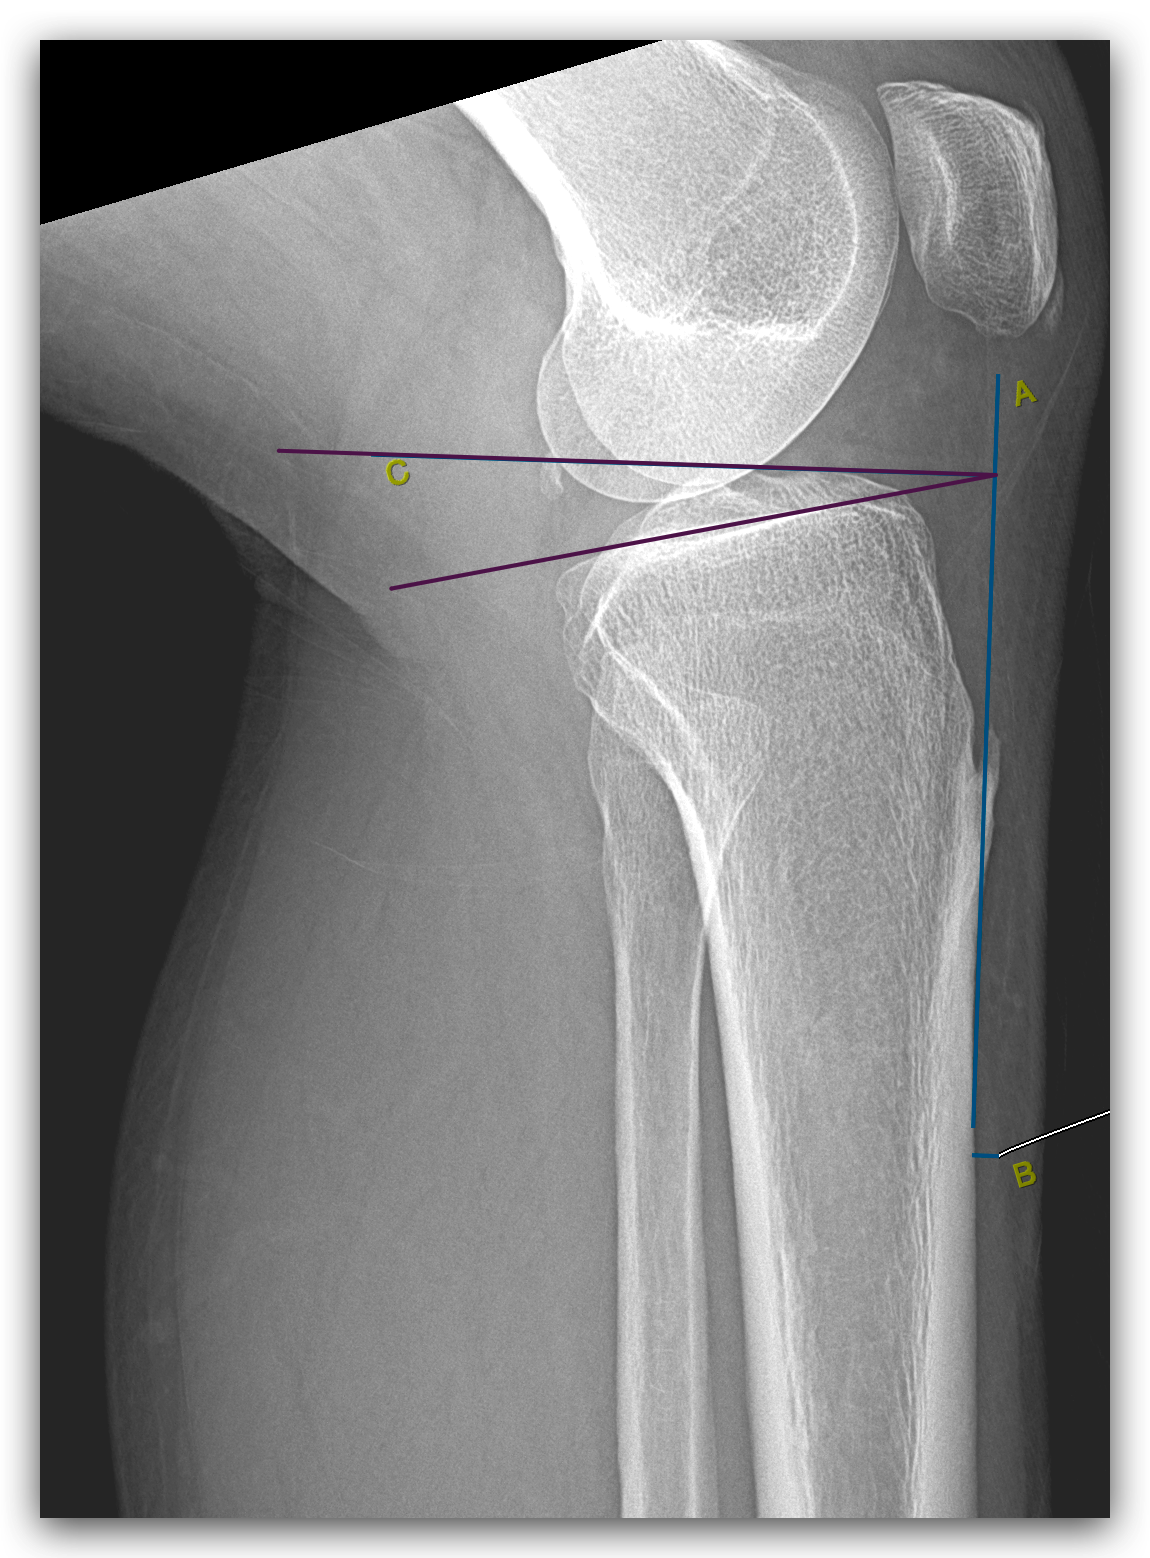

The PTS was measured by the anterior tibial cortex method. A line was drawn along the anterior border of the upper tibial cortex in a lateral radiographic view, which followed the longitudinal axis of the tibial shaft. The uppermost articular surface was then represented by a second line, drawn parallel to the tibial plateau. Moreover, we measured the angle between these two lines, which was the posterior inclination or slope, of the tibial plateau (Fig. 1).

Figure 1: Posterior tibial slope measurement.